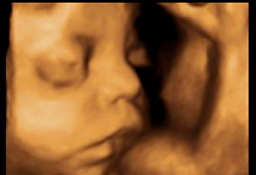

A lo largo del embarazo, el médico te recomendará una serie de pruebas diagnósticas para asegurarse que tu hijo se desarrolla correctamente, como la ecografía. Otras solo se prescriben cuando el ginecólogo sospecha que algo puede ir mal y necesita más datos para corraborarlo, como la amniocentesis o el control del bienestar fetal. Te contamos cómo y cuándo se realizan.